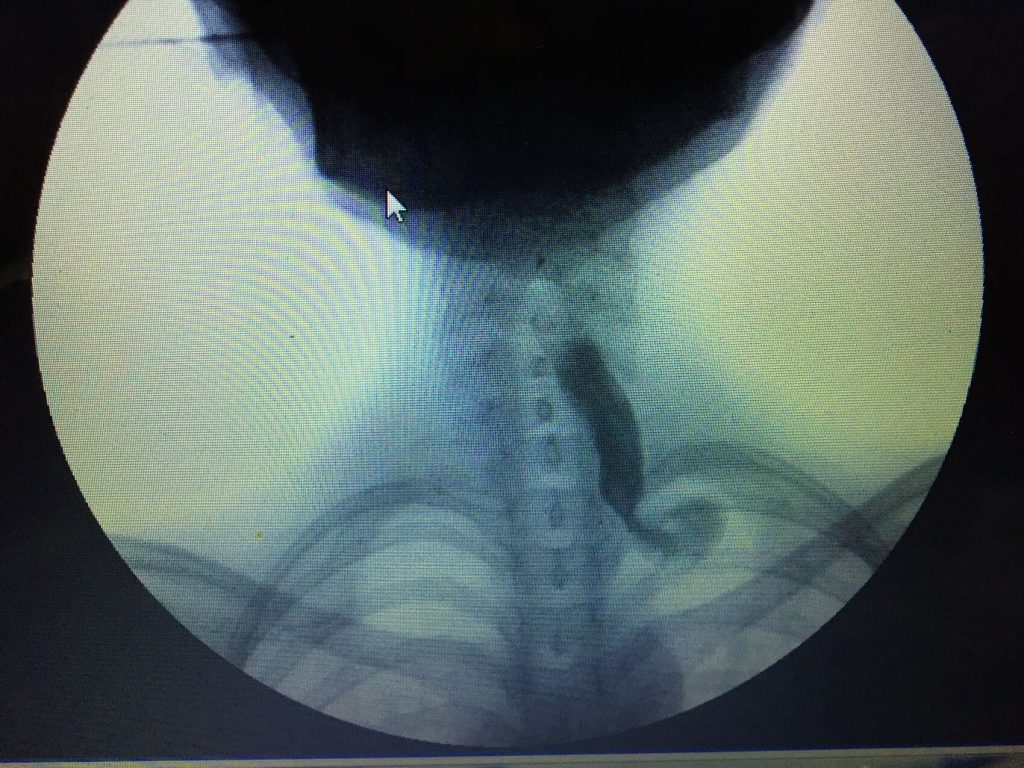

Manejo quirúrgico del cáncer de esófago

Comprende resección del esófago con reconstrucción de la vía digestiva con estómago, colon o intestino delgado.